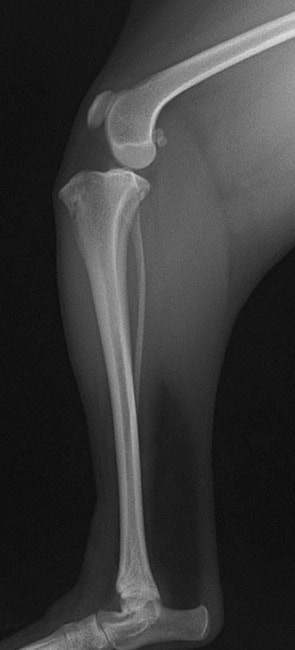

■ 症例22 ポメラニアン 1歳5か月 去勢雄

左後肢の挙上を主訴に来院した。整形学的検査、レントゲン検査より左右の膝蓋骨脱臼(左GradeⅡ〜Ⅲ、右Grade Ⅱ)を認めた。また、脛骨の前方引き出し試験の際に、引き出し兆候は認められないものの、疼痛が認められたため、前十字靭帯の損傷が疑われた。術中における、目視および関節内の操作によって、前十字靭帯の損傷や過伸展といった異常が認められなかったため、膝蓋骨脱臼の整復のみ実施した。手術手技は縫工筋及び内側広筋の解放、脛骨粗面の外側転位、滑車ブロック形造溝術、内外側関節包の縫縮を実施した。本症例は跛行もなく経過良好である。しかし、頸骨高平部の角度(TPA)が 右26.2°、左24.9°であり、解剖学的に前十字靭帯損傷のリスクが高いことから今後の経過に注意が必要である。